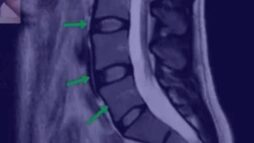

План видеоурока

- Что оценивать на МРТ

- Как выглядит идеальный позвоночник

- Как выглядит плохой позвоночник

- Как выглядит позвоночник спортсмена

- Надрыв кольца на МРТ, поясничный прострел

- Протрузия на МРТ

- Грыжа осложненная стенозом канала

- Секвестрированная грыжа

- Артроз на МРТ

- Позвоночник пациента, занимающегося тяжелым физическим трудом

- Остеопороз, перелом позвонка

- Кисты на суставах

- Гипертрофия фасетки

- Листезы

- Гемангиомы

- Гипертрофия желтой связки

- Грыжа Шморля